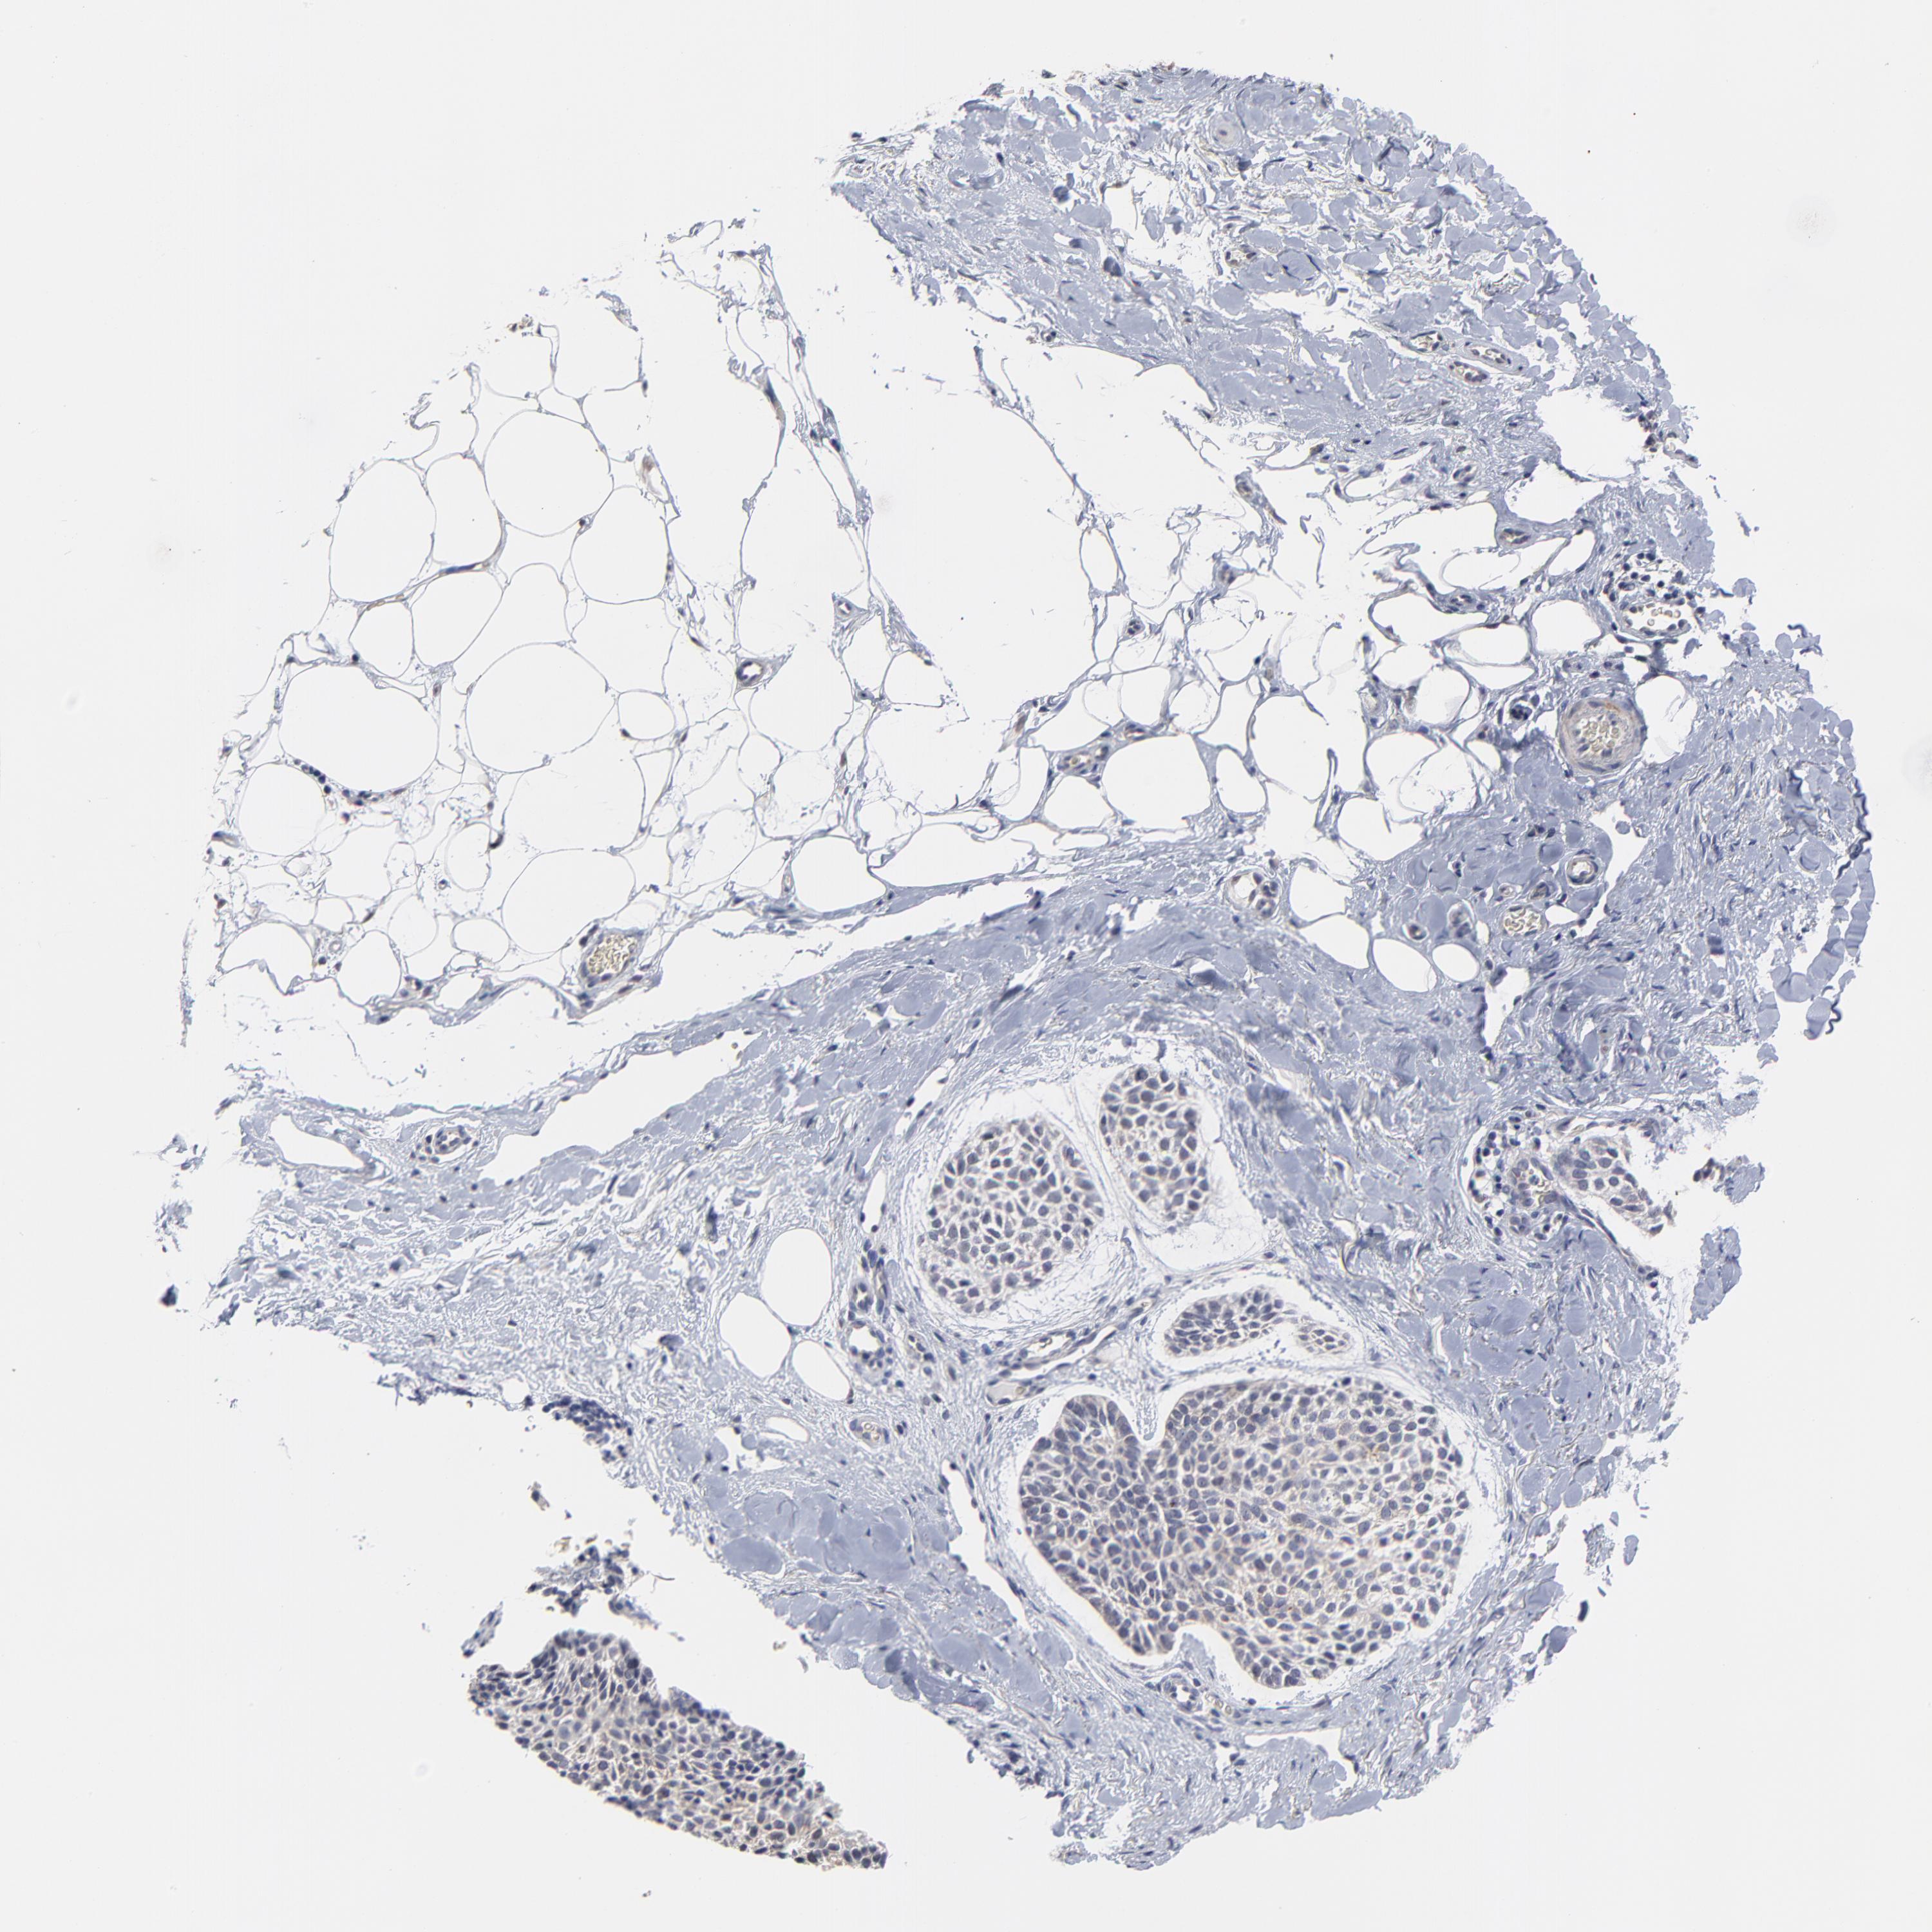

SKIN CANCER - Protein expressioni

A mouse-over function shows sample information and annotation data. Click on an image to view it in a full screen mode. Samples can be filtered based on level of antibody staining by selecting one or several of the following categories: high, medium, low and not detected. The assay and annotation is described here.

Antibody stainingi

Antibody staining in the annotated cell types in the current human tissue is reported as not detected, low, medium, or high, based on conventional immunohistochemistry profiling in selected tissues. This score is based on the combination of the staining intensity and fraction of stained cells.

Each image is clickable and will lead to virtual microscopy that enables deeper exploration of all samples and also displays staining intensity scores, fraction scores and subcellular localization as well as patient and tissue information for each sample.

Antibody HPA003333

Squamous cell carcinoma, NOS

Basal cell carcinoma